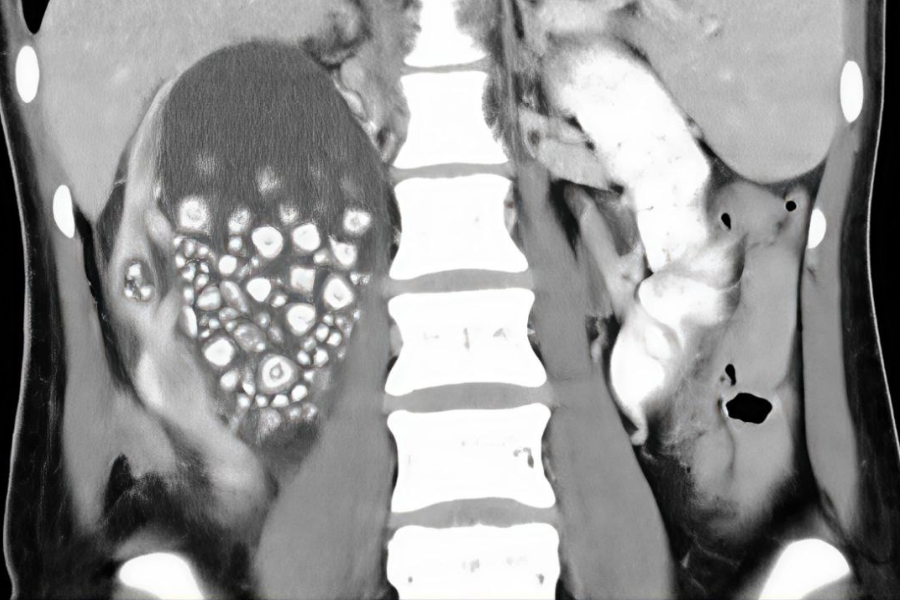

Hasil imbasan ultrabunyi yang dilakukan mendapati, buah pinggang kanan wanita tersebut bengkak dan berlaku pembentukan cecair sehingga pembedahan terpaksa dilakukan.

Hasil pembedahan akhirnya berjaya mengeluarkan lebih 300 biji batu karang dari tubuh wanita tersebut yang dianggarkan berukuran antara dua hingga lima milimeter.